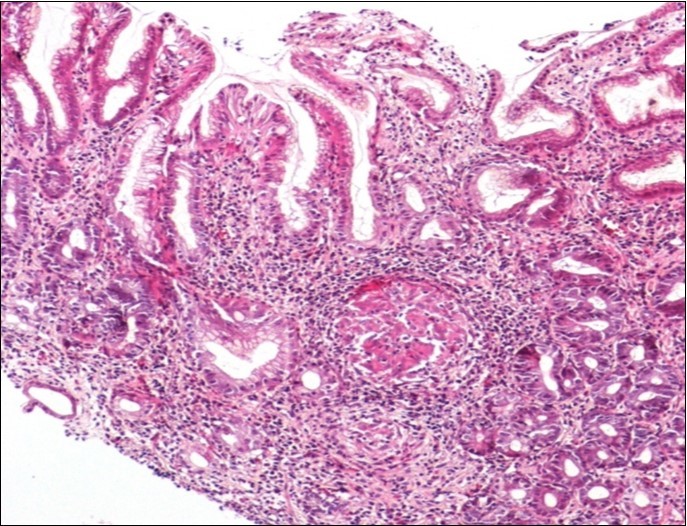

Concerning the etiology, diagnosis was made regarding to the past medical facts, the clinical symptoms, the endoscopic findings and the histological associated lesions. The main etiology was represented by Crohn’s disease in ten cases, followed by gastric tuberculosis in 6 cases. H Pylori was the retained cause of gastric granulomatosis in 5 cases, regarding to the absence of other etiologies, and the favorable issue after antibiotic eradication treatment. In 5 other patients, etiology of gastric granulomatosis was also found and the final diagnosis was a sarcoidosis (n=3), foreign body reaction (n=1), and yersiniosis (n=1). In our series, thirteen cases were unclassifiable despite etiological investigations and no cause of gastric granulomatosis was isolated. Histological findings of a case of tuberculosis and sarcoidosis are represented in Figure 1 and Figure 2.

Figure 1.Histological aspect of gastric granulomatosis secondary to tuberculosis : Antral biopsy specimens revealing multiple necrotizing (caseating) granulomas ( HEx100)